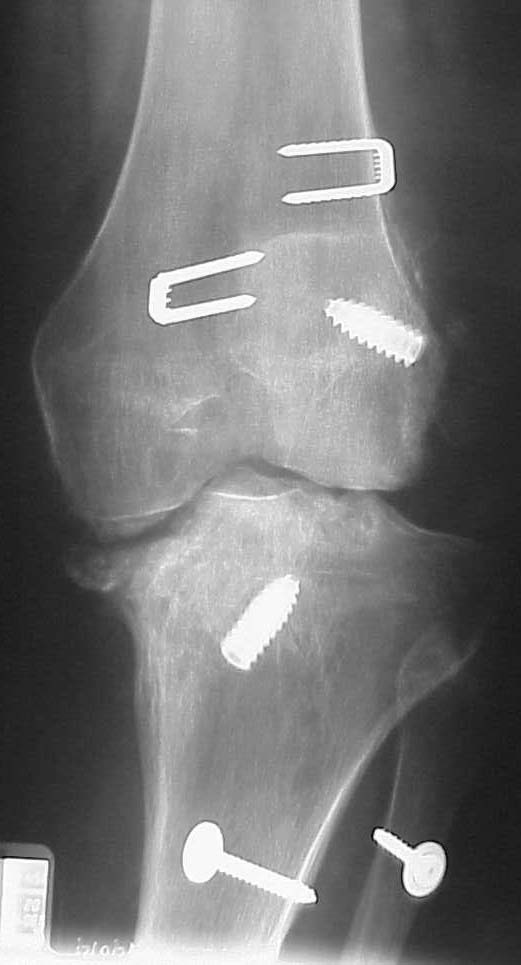

This is a 23 yo male that had a knee dislocation in Oct 2000 w/a popliteal artery injury repair and compartment syndrome and peroneal nerve injury that has not recovered.

He had STSG and delayed ACL/PCL and posterolateral corner reconstruction at 3 weeks. I only have his injury films, but he says his leg always has appeared to be in varus. He has a sedentary job, painless ROM 0-100 degrees, walks w/ slight limp. He made an appointment to establish a new physician as his insurance has changed. His clinical appearance and current xrays are impressive, but he does not seem too concerned. Any thoughts on interventions? He is getting his post reconstruction xrays for review.

AP 18 mos

Varus